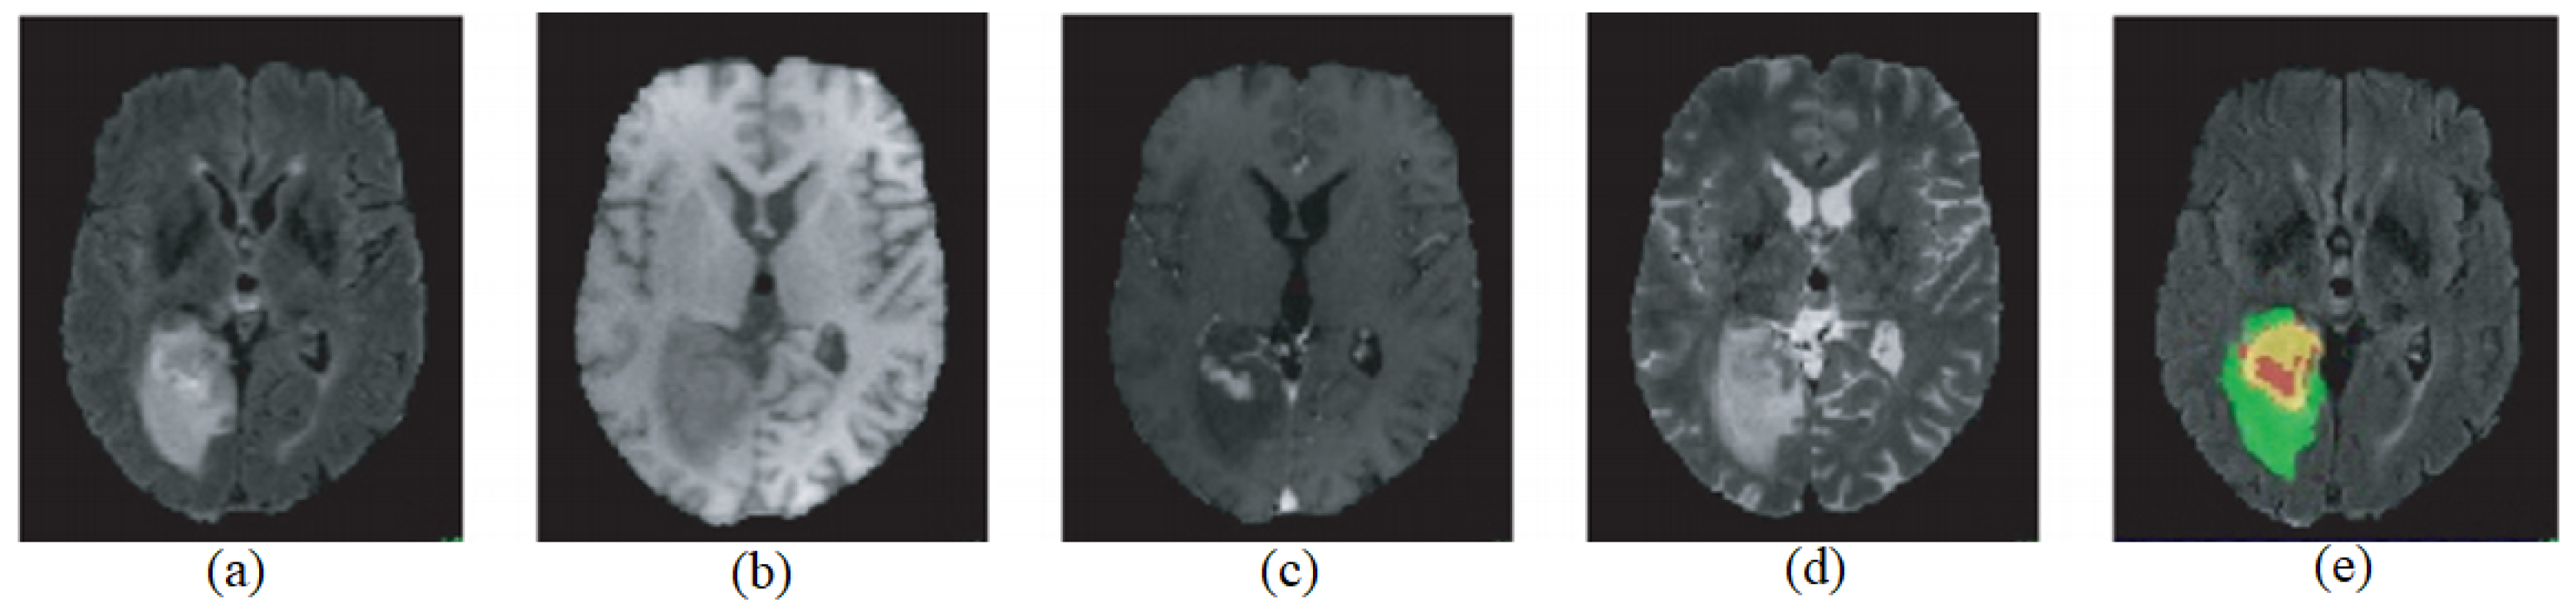

Biomedical imaging has firmly established itself as an integral component of both disease diagnosis and subsequent treatment strategies, with its role continuously expanding [1]. One of the most pressing scientific challenges in the domain of medical imaging is harnessing the potential of artificial intelligence (AI) and deep learning methodologies. The ambition is to adeptly analyze the vast repositories of medical imaging data, ensuring that these technologies not only keep pace with the data influx but also bring transformative advancements to the field. However, while there is an abundance of research on MRI segmentation methods, there remains a noticeable gap in leveraging advanced neural network architectures for efficient and accurate brain tumor segmentation from MR images. Our work addresses this very gap by proposing an innovative method that combines the strengths of multiple existing models. The overarching goal is to arm clinicians with sophisticated tools and methods, facilitating more effective screening, diagnosis, therapeutic planning, image-guided interventions, evaluation of treatment outcomes, and patient monitoring across a myriad of significant medical conditions [2]. Zooming into the specific context of brain tumors, these are characterized by the aberrant proliferation of cells within the cerebral environment [3]. The onset and progression of such tumors can be subtle yet profoundly harmful, significantly affecting a patient’s well-being and overall quality of life. Recognizing these challenges, the medical community has continuously sought better methods for diagnosis and intervention. As a result, as medical advancements progress, technologies like medical imaging, tumor monitoring, and the ability to predict patient outcomes have taken center stage [4]. Yet, there exists a tangible need for automated methods that not only detect these tumors but also predict their progression with higher accuracy. Our research aims to provide a comprehensive solution that bridges this gap, ensuring that individuals receive the most comprehensive and effective treatments available. These advancements are not just about detecting tumors but providing a holistic approach to patient care, ensuring that individuals receive the most comprehensive and effective treatments available [5]. The integration of these technologies underscores their importance in the contemporary treatment of brain tumors [6]. One standout technique in this realm is Magnetic Resonance Imaging (MRI). MRI is a non-invasive imaging method that uses radiofrequency signals to produce internal images by exciting target tissues under a powerful magnetic field. Some of its unique advantages include excellent soft tissue contrast, no radiation exposure, and the capability to offer multi-modal and multi-parameter imaging by varying the contrast agents. This makes MRI particularly suited for detecting brain abnormalities. For brain MRI, there are four commonly used imaging modes (referenced in Figure 1): (a) FLAIR (fluid-attenuated inversion recovery) prominently showcases the edema, or swelling, surrounding brain tumors. (b) T1-weighted images provide clarity in discerning tumor core contours, consisting of enhanced and non-enhanced tumor regions, as well as areas of necrosis. (c) T1C images (T1-weighted contrast-enhanced images) emphasize the area of enhancing tumors. (d) T2-weighted images offer a clear demarcation between the whole tumor region, which includes the tumor core and the surrounding edema, and the healthy tissue areas. The differences between tumor tissue and adjacent normal brain tissue are significant, but they share a high degree of grayscale similarity. Even though there has been substantial progress in brain tumor research, automatically identifying tumor contours and their detailed segmentation within multi-modal MRI remains a challenging task.

Figure 1.

MRI images of brain tumors across various modalities. The original images are presented in the first row, while the images modified using our a contrast-adjusted algorithm [3] are displayed in the subsequent row. (a) FLAIR, (b) T1, (c) T1ce, (d) T2, and (e) ground truth.